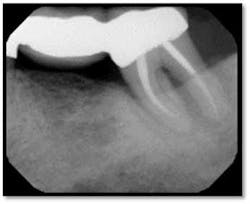

A full set of radiographs taken 13 months post therapy show bone fill in the deepest pockets, with generalized pocket reductions of up to 7mm.

#3 was referred for endodontic evaluation.

#’s 15 and 18 show no signs of endodontic involvement, #15 tests vital.

This patient now has a periodontally stable dentition for the first time in his adult life and is very happy with the outcome of his therapy.